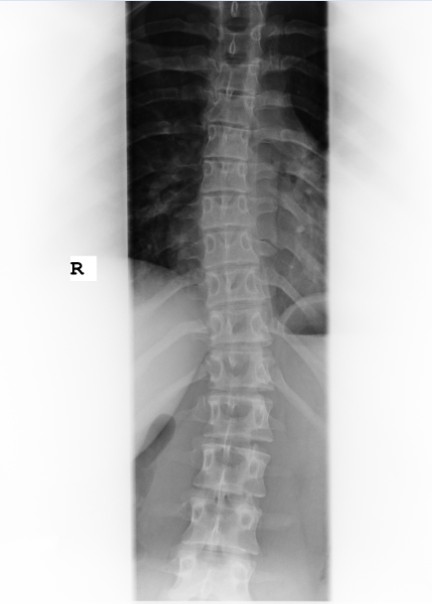

ich hab vorhin noch ne Weile in verschiedenen Threads gelesen und mir noch mal Yasmins Bild vorgeknöpft.

Ich habs Bild jetzt mal abfotografiert und hoffe das es in der 30KB Qualität noch gut zu erkennen ist.

Mit dem anhängen hat es nun geklappt.

Gruß Jaelle

- jassi1.jpg (26.8 KiB) 11471 mal betrachtet

deine Tochter hat keine sooo starke Krümmung, allerdings zu viel, um unbehandelt zu bleiben. Schwer zu sagen, ob die Ausbildung das richtige für sie sein wird. Hat sie in dem Bereich schon Praktikum gemacht? Muss sie darin z.B. viel in gebückter Haltung arbeiten? Was sagt der Arzt, der für die Ausbildung die Jugendschutz-Untersuchung durchgeführt hat?

Also es sind ja lumbal nur ca. 20°, thorakal noch etwas weniger. Thorakal ist auch keine Rotation zu erkennen, lumbal wäre das wohl Grad 1 von 4 nach Nash/Moe.

Ich denke viele hier im Forum wären froh, wenn sie so ein Röntgenbild hätten

Es ist aber nicht ausgeschlossen, dass es sich noch verschlechtern kann.

Das Röntgenbild sieht aber nicht nach einer gravierenden Skoliose aus. Auch würde ich deswegen nicht sofort die Ausbildung wieder absagen.